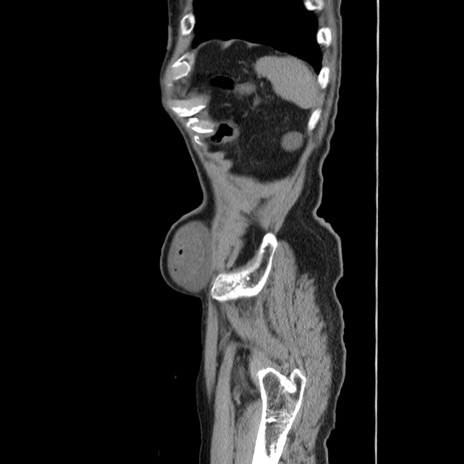

冠状断像

【症例】80歳代男性

【主訴】左側腹部痛、嘔吐

【現病歴】本日早朝より左腹部に痛みあり。昼頃嘔吐認めたため、救急要請。

【既往歴】直腸癌(Mile手術)、胆摘

【身体所見】意識清明、BT 35.9℃、BP 221/93mmHg、SpO2 97%(RA) 、腹部:左ストーマ周囲に限局性の腹部膨隆あり。 膨隆部自発痛・圧痛あり・軟。

【データ】WBC 7700、CRP 0.09